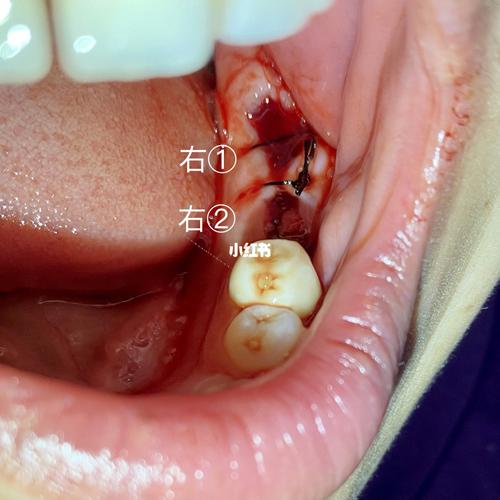

81566拔烂牙根,位点保存→3个月后再种植_止痛药